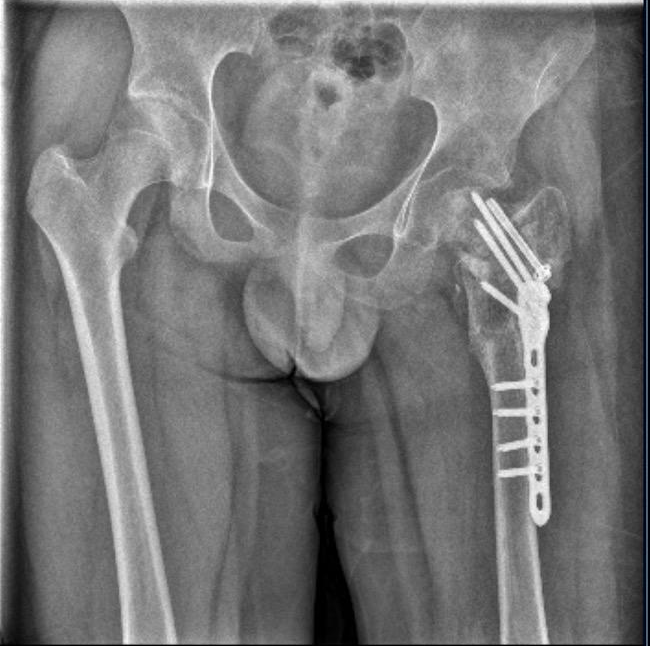

▲小武左股骨陈旧性骨折,打了钢针、钢板 图据受访人

7月,晋江市公安局对小武被故意伤害一案立案侦查。随后,晋江市公安局对小武进行了人体损伤程度鉴定,8月29日出具的《鉴定意见通知书》显示,小武三个部位不同程度损伤,其中,“左髋部重伤二级,胸部轻伤一级,双下肢轻微伤”,同时,其左股骨打了钢针、钢板。